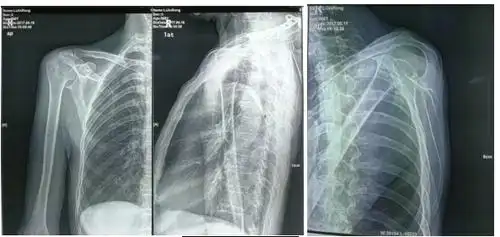

肩关节的摄影体位

肩关节x线检查体位大全